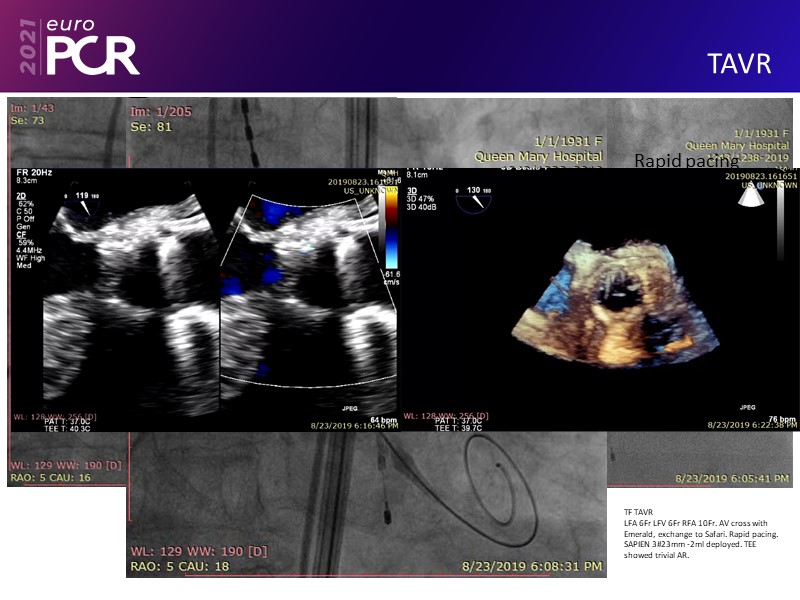

Leave no calcium uncracked--triple vessel disease, severe AS, cardiogenic shock EuroPCR 2021 Clinical Case SPEAKER: J. Fang Previous Next Download presentation